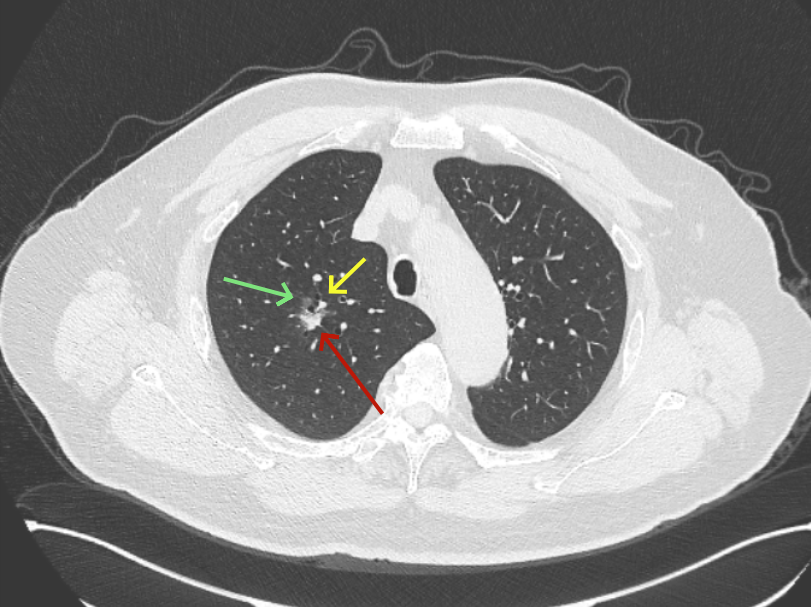

再看2026年3月最近复查时不同层面病灶A的细节影像特征:

微小血管走向病灶,磨玻璃的密度淡而较纯。

病灶A以及他处磨玻璃结节其实进展都是不明显的,略与2022年比,病灶A稍显明显点。病灶B开始时极淡,之前进展虽有但也甚微,直到2025年9月仍是磨玻璃成分为主,只是点状少许密度稍高成分。但在最近半年内却显然进展!若从影像上判断,基本上就得是浸润性腺癌了。那有几点:一是必不能再随访;二是大小来看仍是1A期;三是从快速进展来说,可能含有部分高危亚型,比如微乳头或实体型等;四是他处的磨玻璃结节以及病灶A显然不能用病灶B的转移来解释,仍考虑是多原发早期肺癌。

这是较为少见的一个病例,磨玻璃为主,而且一直瘤肺边界欠清晰的病灶何以会在之前三年均极缓慢微小变化的情况下,近半年却快速进展呢?从影像细节上看,我们能否进一步分析哪种纯磨玻璃结节可能会较快进展?结合本例,我个人的考虑是:1、病灶整体显得是磨玻璃密度,但灶内并不均匀,就如磨玻璃密度中混入细沙状;2、整体轮廓虽然较清但瘤肺边界相对来说却并不太清晰;3、邻近有血管紧挨,而且与病灶这间缺乏间隙;4、病灶密度不高,没有明显实性成分,却有灶内有细支气管通气征,说明肿瘤成分具有收缩力,却与纯磨的收缩不匹配(纯磨一般不太会有明显收缩力)。如果有上面这些特征可能要提高警惕,一是适当较短的随访间隔,二是影像细节变化要更加注意,开始变化意味着已经进入发展期,而非蛰伏期。当然是否在2025年9月时定得手术了?如果是孤立性的病灶B,且位置位于能简单楔形切除的位置,那是可以考虑的。但位置深、两肺多发,切除范围不小,再今年据肺癌诊疗指南中说的混合磨玻璃结节实性成分不足25%是非侵袭性病变,且几乎不会转移,那么按原则仍再随访显然是可以的。本例的随访变化再次表明磨玻璃密度肺癌的诊疗个体化之路仍是很漫长的,按指南原则的随访或诊疗显然不足以覆盖所有病例,总结与经验积累永远在路上。